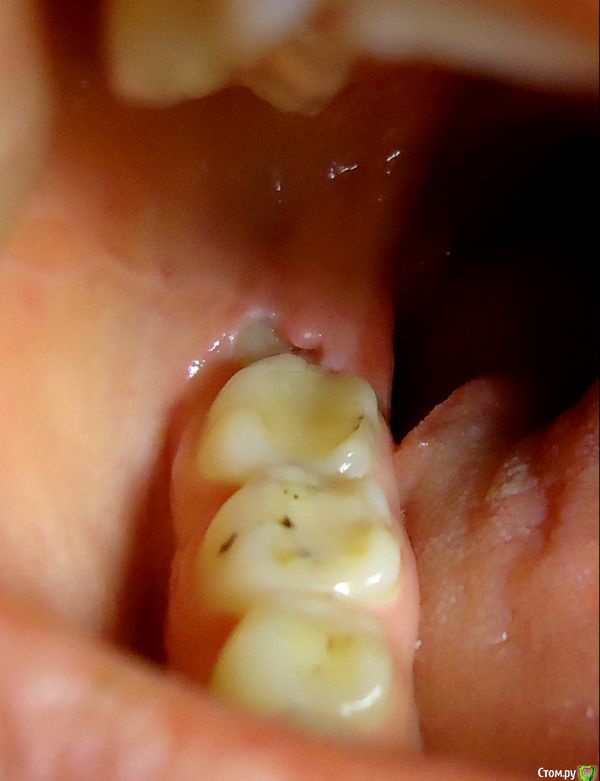

София С Опубликовано 24 ноября, 2017 Автор Поделиться Опубликовано 24 ноября, 2017 (изменено) Большое спасибо за ответы.Есть ещё вопрос:- 38 был удалён вследствие воспаления, нагноения, возникшего под капюшёном, и распространившемся далее, в неблагоприятное время в неблагоприятном месте ( учёба в далёкой азиатской стране ). Там, во время визитов к стоматологу, делались промывки, удаление было отложено к возвращению домой...Теперь 48 - так же закрыт капюшёном, вот снимки. Может, достаточно иссечь его и всё? Визит к хирургу ещё только планируется, снимок 48 сделан заблаговременно, одновременно с 37 Изменено 24 ноября, 2017 пользователем София С Ссылка на комментарий

red_butler Опубликовано 24 ноября, 2017 Поделиться Опубликовано 24 ноября, 2017 4.8 удалять Ссылка на комментарий

igorstom Опубликовано 24 ноября, 2017 Поделиться Опубликовано 24 ноября, 2017 Может, достаточно иссечь его и всё? Визит к хирургу ещё только планируется, снимок 48 сделан заблаговременно, одновременно с 37Когда дело касается: удалять или решить проблему иссечением, то предыдущий опыт должен подсказать решение: если удаление было сложным, а процесс заживления и болезненности достаточно не быстрым, на мой взгляд лучше иссечь. Другой разговор, если Вы будете в недалеком будущем заниматься ортодонтией (то есть исправлять положение зубного ряда), в этом случае лучше заблаговременно удалить восьмой зуб. То что мы часто советуем пациентам не значит, что точно также поступаем со своими зубами. Был у меня случай, когда у меня лечился мой близкий товарищ и коллега стоматолог-ортопед. С руками у него всё порядке. И когда я возразил ему, мол, ну ты же сам ортопед и знаешь, что в твоем случае показана вкладка и коронка, он чуть ли не со слезами: "Игорь, я не хочу коронку!". 1 Ссылка на комментарий

igorstom Опубликовано 25 ноября, 2017 Поделиться Опубликовано 25 ноября, 2017 Ну тогда лучше удалить. "С глаз долой, из сердца вон". Всё равно, рано или поздно придется от него избавиться. Почему? Изначально непрорезавшиеся полностью или кривовато, восьмые сложнее поддаются адекватной гигиене и самоочищаемости. И соответственно быстрее разрушаются. И часто способствуют разрушению стенки соседнего 7-го зуба, с краями которого соприкасаются. Ссылка на комментарий